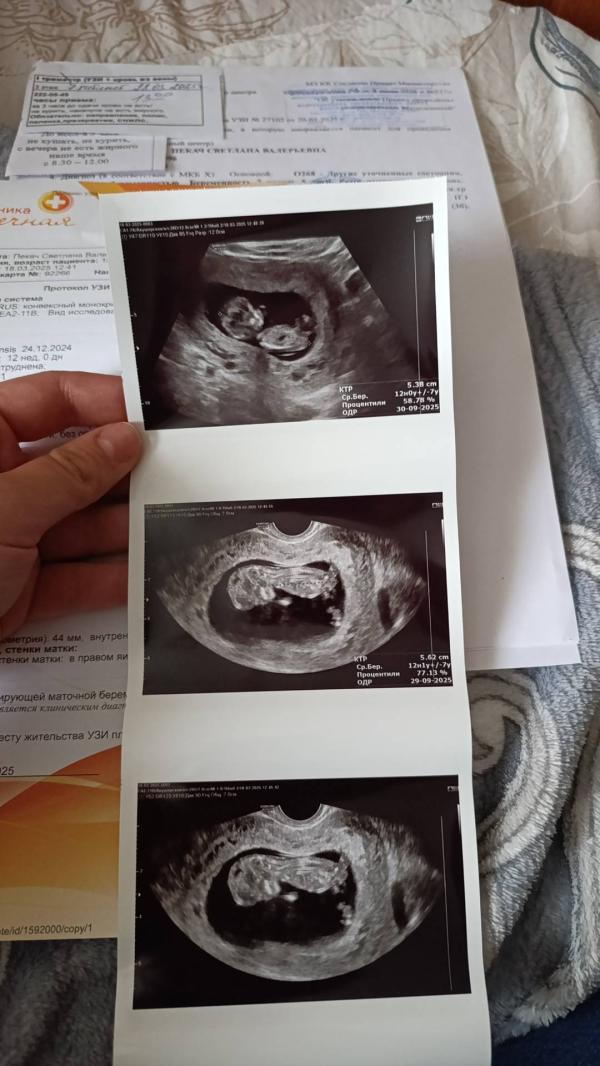

Я оделась забрала документы . иду в регистратуру. Женщина говорит , у вас ктр даже до 45 не доходит ... Вам звур не ставили ?

Приехала в клинику , только зашла в кабинет , Элеонора Александровна успокаивает , говорит не переживай все посмотрим . Смотрит вагинально и по животу . развернула мне монитор, ребёнок активный , носик в порядке , твп 1.1 , говорит , странно , вполне можно было сделать скрининг , все абсолютно в порядке , ктр 53 , все соответствует сроку .